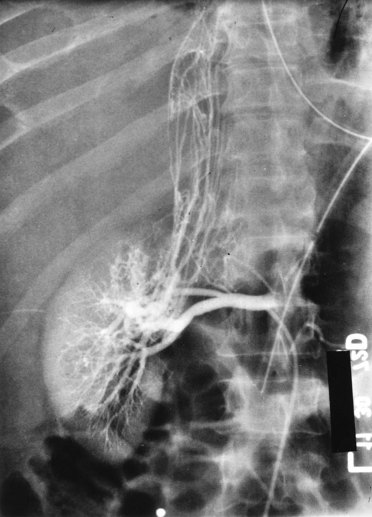

Patients who undergo nephron-sparing surgery for RCC may be left with a relatively small amount of renal tissue and are at risk for development of long-term renal functional impairment from hyperfiltration renal injury (Modlin and Novick, 2001; Abdi et al, 2003; Lane et al, 2009; Novick, 2009). In a study of 14 patients observed for up to 17 years after PN in a solitary kidney, patients with more than 50% reduction in overall renal mass were found to be at increased risk for development of proteinuria, focal segmental glomerulosclerosis, and progressive renal failure (Novick et al, 1990). The development of proteinuria correlated directly with the length of follow-up and inversely with the amount of remaining renal tissue. Renal biopsy revealed focal segmental glomerulosclerosis in several patients with severe proteinuria (Fig. 49–21). These findings mirror those observed in experimental animal models of partial renal ablation (Brenner, 1983). Because proteinuria is the initial manifestation of this phenomenon, a 24-hour urinary protein measurement should be obtained yearly in patients with a solitary remnant kidney to screen for hyperfiltration nephropathy.

Figure 49–21 A, Ten years after partial nephrectomy for large tumor in solitary left kidney, intravenous pyelogram shows function of small renal remnant. The patient had developed nephrotic syndrome at this time. B, Renal biopsy specimen shows focal segmental glomerulosclerosis indicative of hyperfiltration nephropathy.